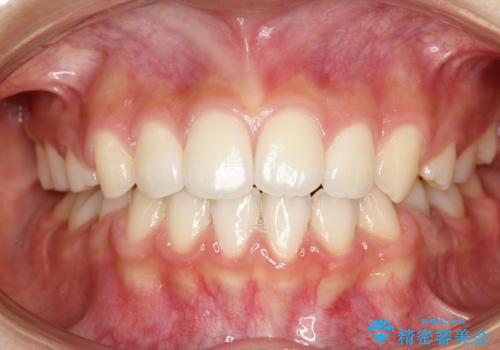

抜歯矯正により前歯の位置が後ろに下がり、わずかではありますが、口元に改善がみられ、歯並びもきれいに整いました。